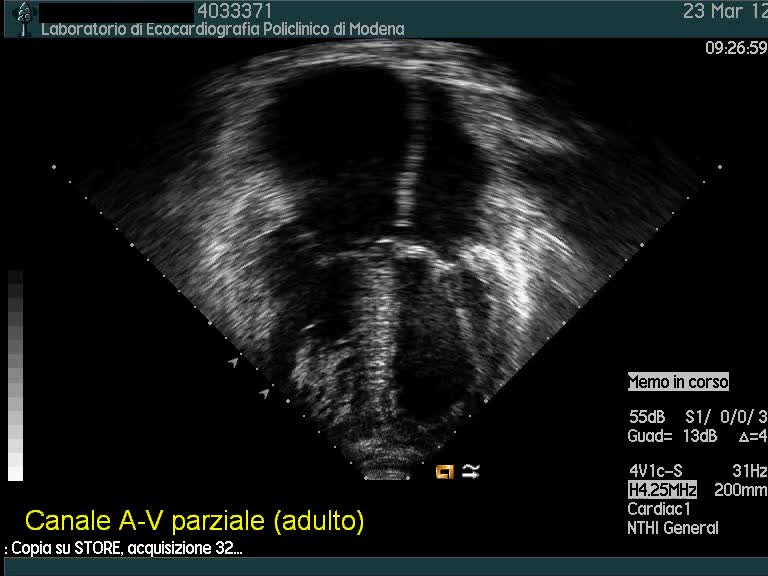

Titolo:

Dia ostium primum (canale av)

Autore:

Andrea Barbieri